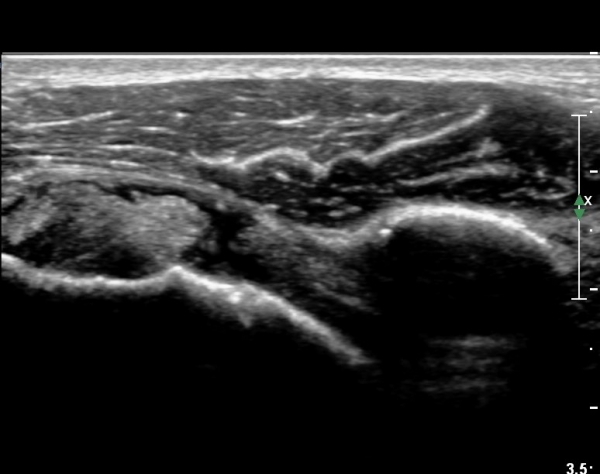

ÃÊÀ½ÆÄ ¼Ò°ß :  È¸Àü±Ù°³°£°Ý °Ë»ó»ó ±Ø»ê°ÇÀº Á¤»ó¼Ò°ßÀ» º¸À̳ª °ß°©ÇϱٰÇÀº Àú¿¡ÄÚ ¿¬°á¼º ¼Ò½ÇÀÌ

º¸¿© °ß°©ÇÏ±Ù°Ç ÆÄ¿­ÀÌ ÃßÁ¤µÈ´Ù(»çÁø 1). ŽÃËÀÚ¸¦ ¾à°£ ¾Æ·¡·Î À̵¿ÇÑ ÈÄ